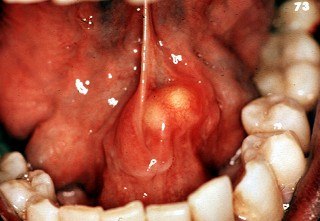

K11.2 Сиаладенит

Сиалоаденит